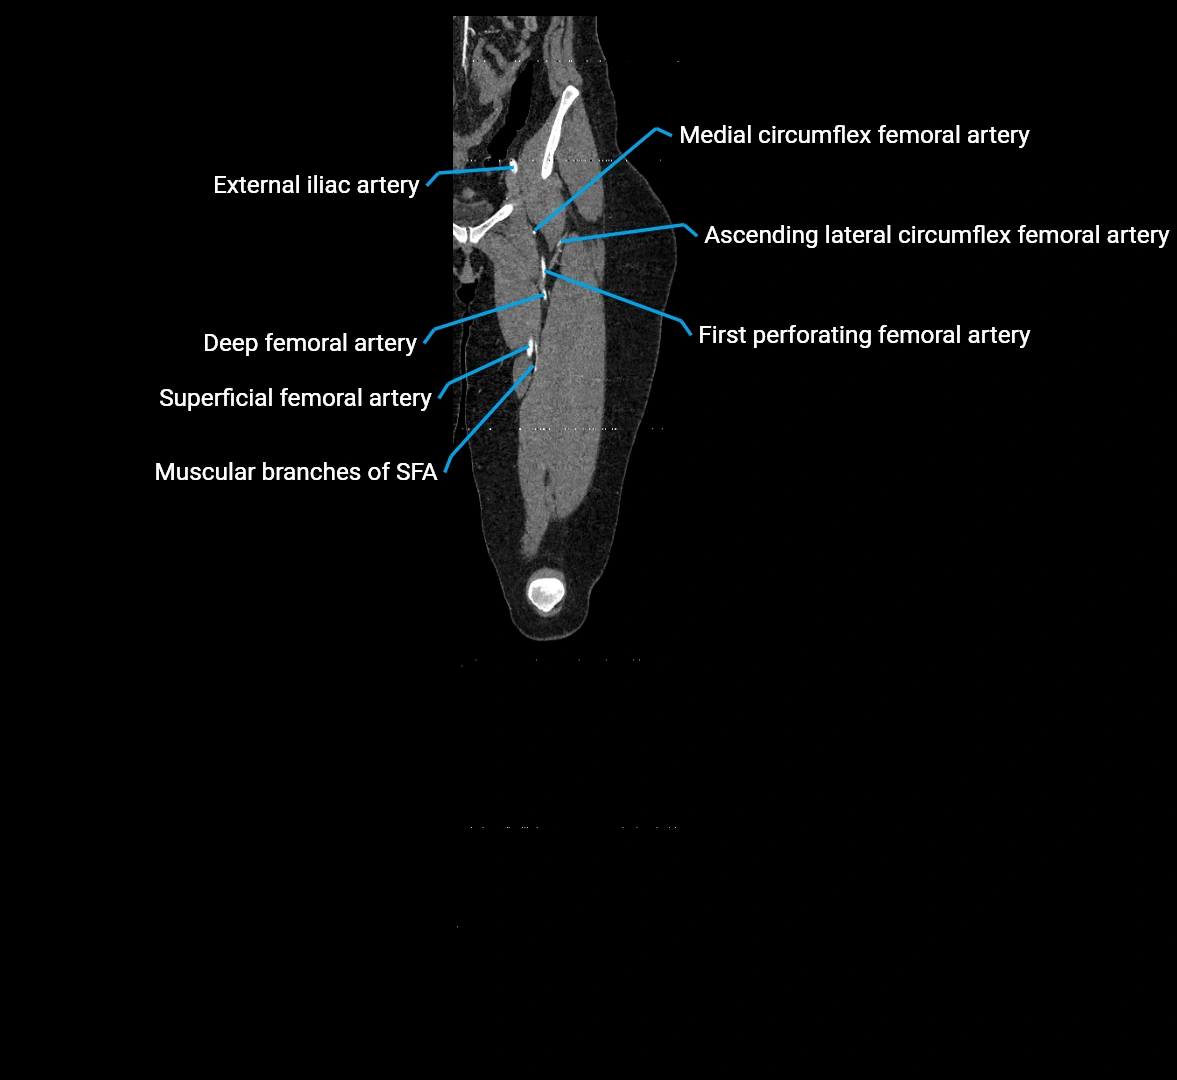

CT Appearance

Non-contrast CT:

• Appears as a tubular soft tissue structure anterior to vertebral bodies

• Calcified atherosclerotic plaques appear as hyperdense foci along the wall

• Useful for screening abdominal aortic aneurysm (AAA) size and mural calcification

Contrast-enhanced CT (CTA):

• Gold standard for abdominal aortic imaging

• Provides excellent detail of lumen, wall, aneurysm, thrombus, and branch vessels

• Multiplanar and 3D reconstructions help in aneurysm measurement, stent graft planning, and dissection evaluation

• Detects acute rupture, traumatic injury, or occlusion with high sensitivity